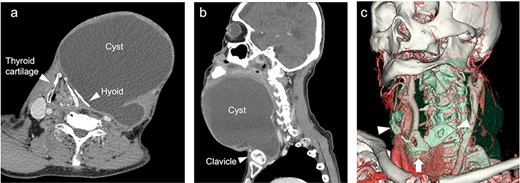

The neck cyst slowly enlarged, and the patient visited the clinic again in 2021. He had developed mild dysphagia and an oppressive feeling in his throat without pain, dysphonia or hoarseness. Physical examination revealed a huge soft mass on his anterior neck toward the left side, extending from the mandible to the clavicle (Fig. 1a and b). A CT scan exposed a lobulated cystic mass, measuring 18 × 16 cm, extending from the tongue base to the inferior level of the clavicle, forcing the thyroid cartilage toward the right side (Fig. 2a and b). The cyst had dislocated the hyoid bone below the upper level of the thyroid cartilage (Fig. 2c). The thyroid gland showed a normal appearance and position. Flexible laryngoscopy revealed marked swelling of the tongue base and a false vocal cord on the left side, narrowing the airway (Fig. 3a and b).

CT scan imaging of the cyst (a, b). The thyroid cartilage pressed toward the right side and dislocation of the hyoid bone (c) 3D-imaging of CT scan. Deformed hyoid bone (arrowhead) and pressed thyroid cartilage (arrow).